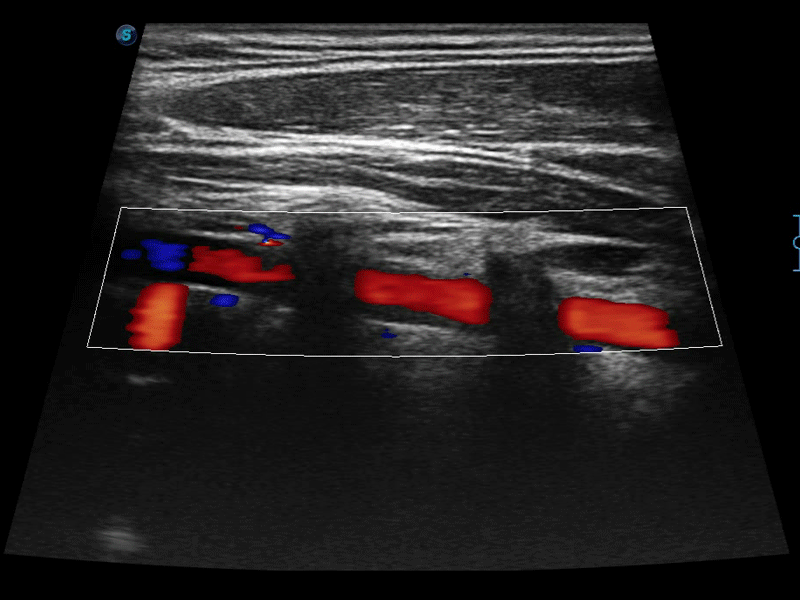

高分辨率血流成像技術(shù)提高了對(duì)低速血流信號(hào)的檢測(cè)能力。在提高空間分辨率的同時(shí),也克服了血流外溢現(xiàn)象,為用戶提供更加真實(shí)的血流動(dòng)力學(xué)信息。

凸陣、線陣和相控陣探頭進(jìn)行實(shí)時(shí)掃描時(shí),開啟擴(kuò)展成像模式,可以擴(kuò)展超聲圖像視野,以便更完整地查看大的病灶或組織器官的解剖結(jié)構(gòu)。

通過色彩血流和實(shí)時(shí)寬景相結(jié)合,可觀察到完整的靜脈或動(dòng)脈的血流,方便醫(yī)生檢查。實(shí)時(shí)掃查過程中,如有任何操作失誤也可以很容易地進(jìn)行回掃擦除,而不會(huì)中斷掃查。